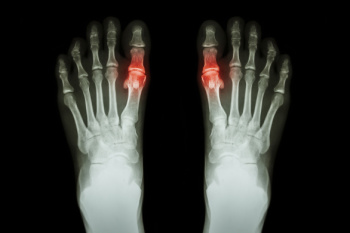

Gout is a form of arthritis marked by sudden, intense joint pain, often starting with the big toe. This condition occurs due to the accumulation of uric acid crystals in the joint, causing inflammation. Symptoms typically include severe, throbbing pain that may begin unexpectedly, often at night. The affected joint becomes swollen, red, and warm to the touch, and even light pressure from clothing or bedding can be excruciating. Warning signs of an impending gout attack include persistent joint discomfort, frequent episodes of pain, or swelling without a clear cause. If you have any of the above symptoms, it is suggested that you consult a podiatrist who can help to manage this condition.

Gout is a type of arthritis caused by a buildup of uric acid in the bloodstream. It often develops in the foot, especially the big toe area, although it can manifest in other parts of the body as well. Gout can make walking and standing very painful and is especially common in diabetics and the obese.

Gout can easily be identified by redness and inflammation of the big toe and the surrounding areas of the foot. Other symptoms include extreme fatigue, joint pain, and running high fevers. Sometimes corticosteroid drugs can be prescribed to treat gout, but the best way to combat this disease is to get more exercise and eat a better diet.